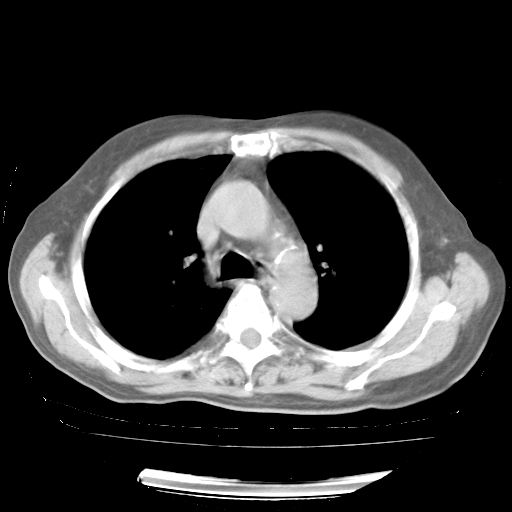

轻微咳嗽,无痰,(体温正常时)R20次/分,P75次/分,双肺底、腋下可闻及少量捻发音。下肢轻度浮肿。

ECG:右心室增大

心脏超声检查:无右心室增大。